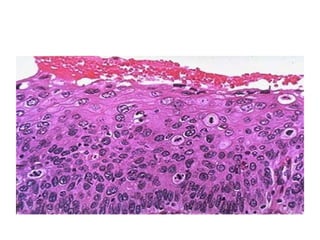

Papilloma of the tongue

Microscopical appearance of squamous papilloma

• 11.

Microscopical appearance ofsquamous papilloma

• #31 This epithelium shows severe dysplasia: Note that dysplastic basal cells characterized by cuboidal shape, high nuclear cytoplasmic ratio, hyperchromatism, mitotic activity, and some loss of orientation to the basement membrane, occupy the lower two thirds of the surface rather than just the basal row of cells. More differentiated cells which occupy the outer third, though still retaining some dysplastic nuclear features have the appearance of maturing squamous cells rather than basal cells, and eventually become flattened on the surface .